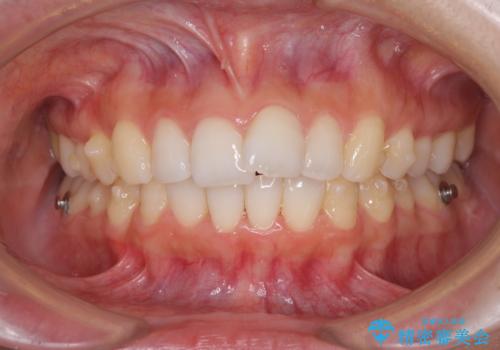

口が閉じにくい 1本飛び出した前歯の矯正治療

- 1本飛び出した前歯を治したいとのことで来院された患者様です。

歯列全体の拡大とIPR(歯と歯の間を削る)によってデコボコが解消するようにし、さらにゴムかけを活用して右側の咬み合わせ位置を変えるように設計し、インビザラインにより治療を行うこととしました。

結婚式までに前歯を整えたいとのことでしたが、インビザラインでは先に奥歯を移動させてから前歯を動かすため、間に合わない可能性がありました。しかし、結婚式までに期間があったことと、マウスピースをしっかりと装着してくださったことで、十分な歯列に整えることができました。